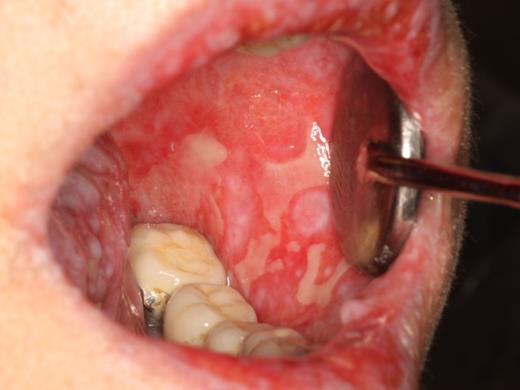

Oral mucosal cGVHD is characterized by lichenoid inflammation that can involve all intraoral sites, but particularly affects the tongue and buccal mucosa.8,13,14 Clinical signs include white hyperkeratotic reticulations and plaques, erythematous changes, and ulcerations, which can range from very limited disease with only mild reticulation to more extensive disease with painful ulcerations (Figures 1 and 2). Of note, the soft palate is infrequently affected, and cGVHD changes rarely extend posteriorly to the oropharynx (Figure 3).13 The lips are also a frequent site of involvement, demonstrating the same changes observed intraorally, and can be a source of significant discomfort (Figure 4).

cGVHD of the buccal mucosa with extensive multifocal areas of ulceration interspersed with erythema and reticulation.